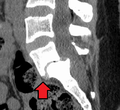

X-ray picture of a grade 1 isthmic spondylolisthesis at L4-5